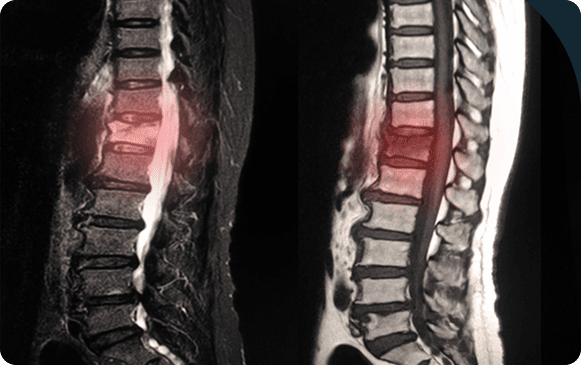

Spine surgery is necessary for certain back pain cases to prevent complications or improve quality of life. It treats various spine conditions such as herniated discs, scoliosis, and spinal fractures, using the latest surgical methods to ensure effective recovery and long-term relief.

Degenerative Disc Disease: A condition where spinal discs deteriorate, causing back or neck pain. Treatment often includes pain management, physical therapy, and non-surgical methods, with surgery considered in persistent cases.